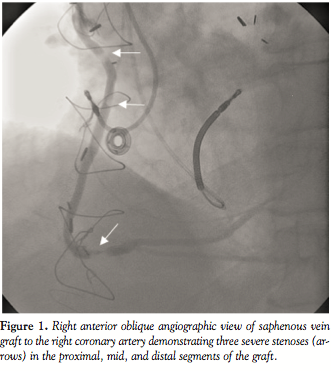

Coronary and graft angiography revealed patent bypass grafts with

three tandem stenoses of 80–90% involving the proximal, mid, and distal segments of the saphenous vein graft (SVG) to the right coronary artery (Figure 1). PCI was performed successfully with deployment of three non-overlapping bare-metal stents without the use of a distal embolization protection device due to lack of sufficient distal space in the SVG for positioning. However, during final stent deployment, perforation of the distal segment of the SVG with extravasation